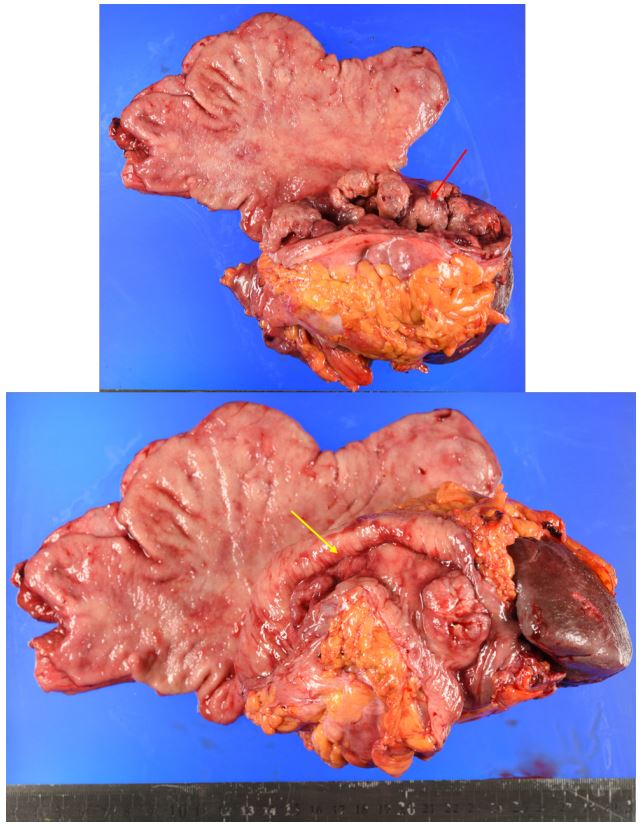

An eighty-year-old woman presented with the symptoms of abdominal pain, slight fever of 37-38°C, and body weight loss. Upper Gastrointestinal (GI) examination performed one month prior to presentation revealed a gastric tumor, while Esophagogastroduodenoscopy (EGD) showed a type 3 tumor in the gastric fundus and corpus (Figure 1a). However, food residues covering the tumor surface prevented precise observation. Colonoscopy revealed an irregular surface elevation in the splenic flexure of the colon (Figure 1b), in which an adenocarcinoma was detected by biopsy. Contrast-enhanced computed tomography (eCT) revealed advanced GC with extensive invasion of the transverse colon, spleen, and pancreas (Figure 2a,b). Peritoneal dissemination and lymph node metastasis were suspected. The eCT image also showed gas in the pancreatic duct, indicating fistulation from the stomach to the pancreatic duct due to tumor invasion (Figure 2b). This fistula was presumed to be the cause of the patient’s low-grade fever. Thus, relatively rapid surgery was performed to control bacterial infection of the pancreatic duct and ensure resection of the advanced GC. Open surgery was performed, and extensive invasion of the GC into the pancreas and transverse to the descending colon was detected. Fortunately, no obvious peritoneal dissemination was observed. Therefore, a total gastrectomy with D2 lymphadenectomy combined with distal pancreatectomy, partial colectomy, and cholecystectomy was performed. Cholecystectomy was added as it is performed along with total gastrectomy as the standard procedure in our institute. The resected gastric tumor measured 160×80 mm (Figure 3a). Pathological tests revealed a poorly differentiated adenocarcinoma of the stomach invading the pancreas, transverse colon, and splenic serosa (Figure 3b-e). No metastasis was identified in the dissected lymph nodes or peritoneum. The pathological cancer stage was IIIA, according to both the TNM Classification of Malignant Tumours-8th edition [13] and the 15th edition of the Japanese Classification of Gastric Carcinoma[14]. Approximately two months after surgery, we initiated adjuvant chemotherapy with tegafur/gimeracil/oteracil, which was discontinued after only two months due to severe adverse events. Two years after surgery, the patient remains alive without relapse.

Figure 3a: Macroscopic view of the en-bloc resected specimen including the stomach, spleen, transverse colon, pancreatic body, and tail. The primary gastric cancer lesion and invasion to the transverse colon are highlighted with red and yellow arrow, respectively.

Figure 3b: H&E image of the primary gastric cancer

Figure 3c,d: Invasion of the gastric cancer to the transverse colon (c), pancreas (d).

Figure 3e: Cancer in the adhesional tissue on the surface of the spleen (red arrow).